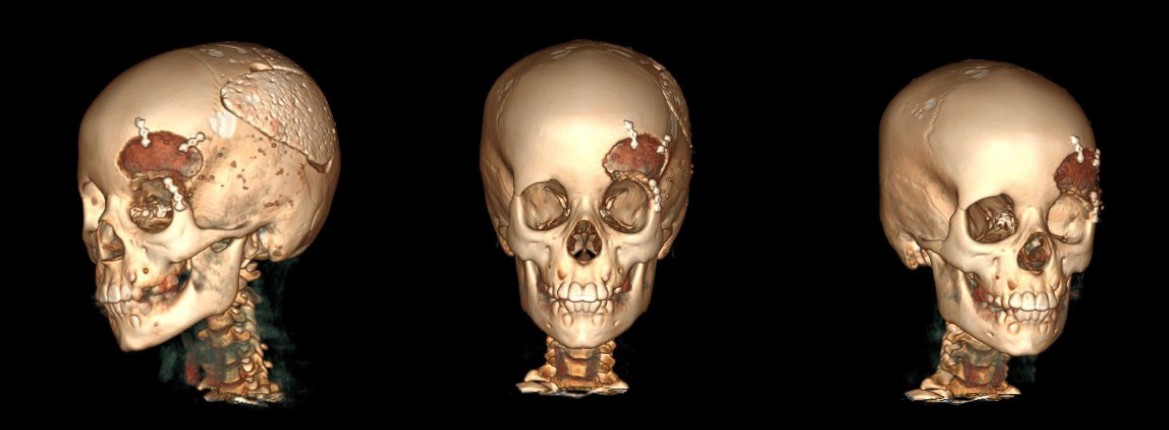

The MSCT imaging revealed affected osseous structure diffuse ill-defined expansible ground glass lesion appearance involving craniofacial region. Notably there was a periosteal thickening along the anterior surface of the left frontal and partial bone. Clinically, a change in the configuration of the face was visualized without pain (Figures 1, 2).

Fig. 1. MSCT (3D cut) showing bony expansion over the left frontal bone region in preoperative stage on 2022

Fig. 2. Preoperative axial computed tomographic image exhibiting characteristic ground-glass opacification of fibrous dysplasia involving the left frontal